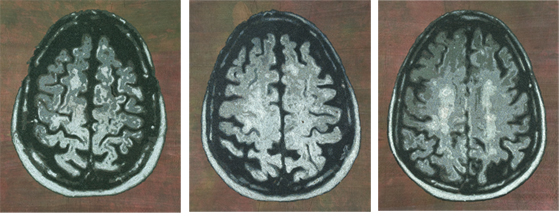

M.S. Study Paula 1

M.S. Study Paula 2

M.S. Study Paula 3